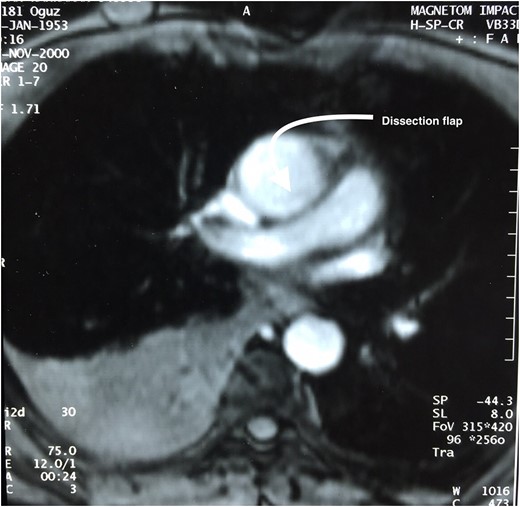

Coronary angiography revealed a lesion on OM1 (80–90%) on its midportion where by the other coronary arteries were normal. On operation, following standard cannulation aortotomy was done where by the left main coronary artery osteal on the ascending aorta position was found to have a chronic dissection flap with dimension of 15 mm × 30 mm in size (Fig. 2). Dissection flap was resembling a mobil atheroma with free-floating tip. That the case being, modified Bentall procedure, CABG on OM1 and mitral valve replacement was perfomed.

A picture that shows a chronic dissection flap of a patient during surgery.